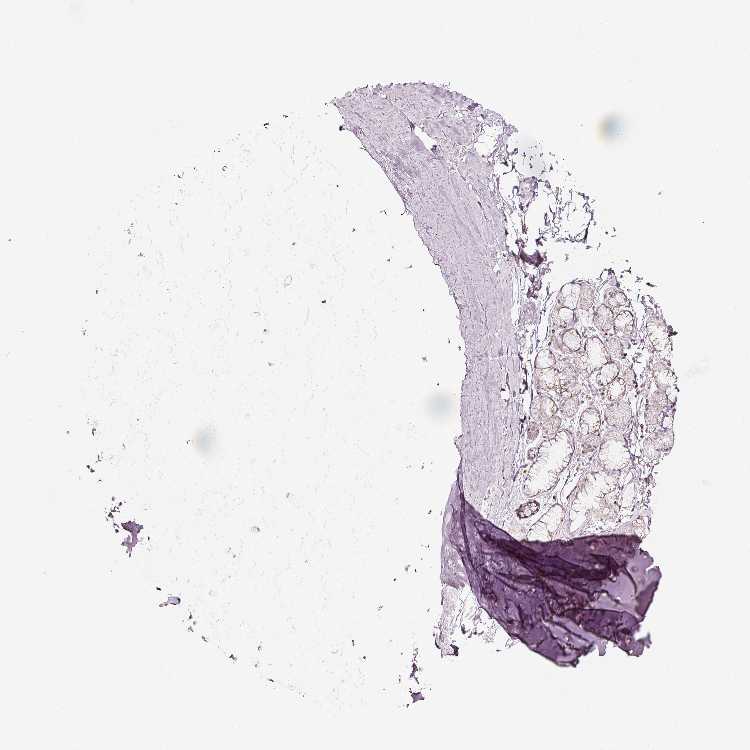

SOFT TISSUE 1 - Antibody stainingi

Antibody staining in the annotated cell types in the current human tissue is reported as not detected, low, medium, or high, based on conventional immunohistochemistry profiling in selected tissues. This score is based on the combination of the staining intensity and fraction of stained cells.

Each image is clickable and will lead to virtual microscopy that enables deeper exploration of all samples and also displays staining intensity scores, fraction scores and subcellular localization as well as patient and tissue information for each sample.

Antibody HPA011249Antibody CAB015227

Chondrocytes LowNot detected

Fibroblasts LowNot detected